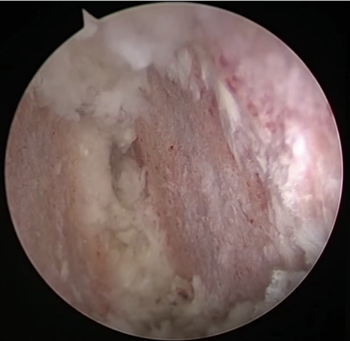

内镜下可见软骨终版相比传统手术处理更彻底